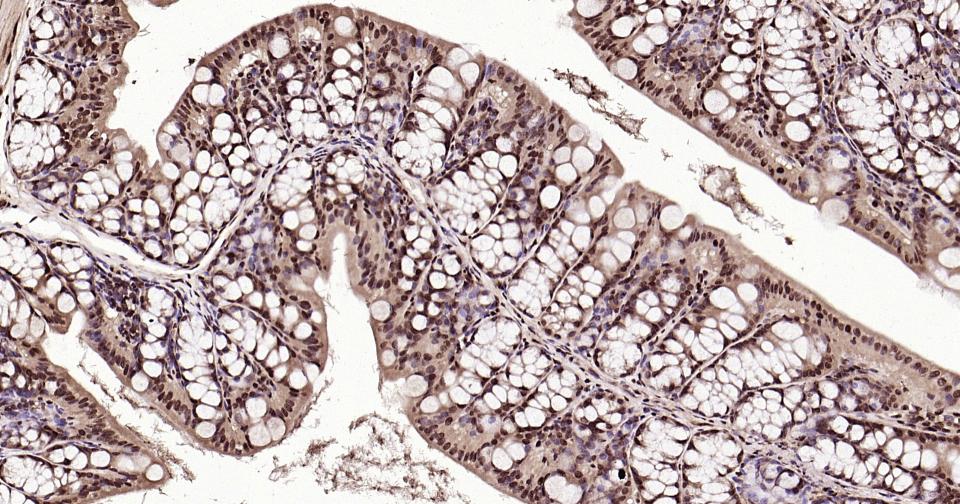

Paraformaldehyde-fixed, paraffin embedded Mouse Colon; Antigen retrieval by boiling in sodium citrate buffer (pH6.0) for 15 min; Antibody incubation with K27-linkage specific ubiquitin Monoclonal Antibody, Unconjugated(bsm-63007R) at 1:200 overnight at 4°C, followed by conjugation to the bs-0295G-HRP and DAB (C-0010) staining and DAB (C-0010) staining.